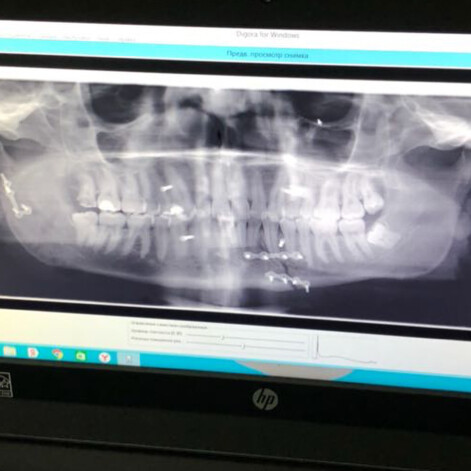

На прошлой неделе в одном из баров Перми произошло нападение на Андрея Ширмана, более известного как DJ Smash. Артисту сломали челюсть, поэтому он не может говорить. Весь интернет облетели фотографии, на которых музыкант запечатлен на больничной койке с гематомами.

По некоторым данным, Андрея попросили о совместной фотографии, на что он ответил отказом. После этого завязалась драка, в инцидент вмешались сотрудники службы безопасности бара. Получив первую медицинскую помощь, музыкант улетел в Москву. Сейчас Ширман находится в одной из московских больниц, где ему сделали операцию на лице. DJ Smash утверждает, что его избил экс-депутат Законодательного собрания Александр Телепнев, однако тот отрицает свою причастность к нападению на артиста.